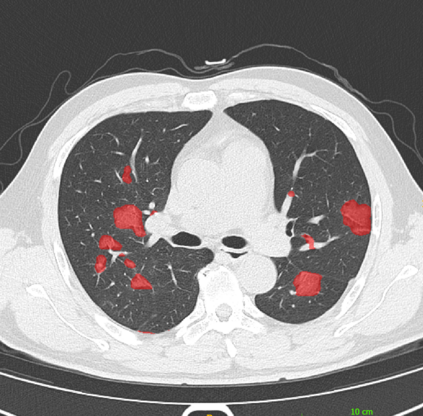

The COVID-19 pandemic has had a considerable impact on day-to-day life. Tackling the disease by providing the necessary resources to the affected is of paramount importance. However, estimation of the required resources is not a trivial task given the number of factors which determine the requirement. This issue can be addressed by predicting the probability that an infected patient requires Intensive Care Unit (ICU) support and the importance of each of the factors that influence it. Moreover, to assist the doctors in determining the patients at high risk of fatality, the probability of death is also calculated. For determining both the patient outcomes (ICU admission and death), a novel methodology is proposed by combining multi-modal features, extracted from Computed Tomography (CT) scans and Electronic Health Record (EHR) data. Deep learning models are leveraged to extract quantitative features from CT scans. These features combined with those directly read from the EHR database are fed into machine learning models to eventually output the probabilities of patient outcomes. This work demonstrates both the ability to apply a broad set of deep learning methods for general quantification of Chest CT scans and the ability to link these quantitative metrics to patient outcomes. The effectiveness of the proposed method is shown by testing it on an internally curated dataset, achieving a mean area under Receiver operating characteristic curve (AUC) of 0.77 on ICU admission prediction and a mean AUC of 0.73 on death prediction using the best performing classifiers.